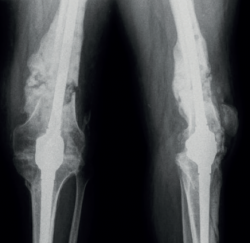

retla.05109.fs2201005-figura6.png

Figura 6. Control radiológico al año, donde se observa la fusión articular y la integración del injerto óseo.

En el control al año el paciente no ha presentado ningún signo de reactivación de la infección con los reactantes de fase aguda dentro de la normalidad. Se ha recuperado parcialmente de la parálisis del CPE y deambula sin ayuda de muletas (Figura 6).